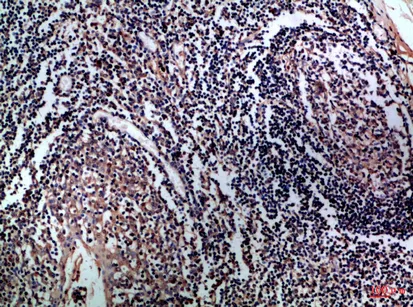

CD1A/B Rabbit Polyclonal Antibody($99/20μL)

Cat: APRab08259

Size1:20μL Price1:$99

Size2:50μL Price1:$118

Size3:100μL Price2:$220

Size4:200μL Price3:$380

Application:IHC-P,IF-P,IF-F,ICC/IF,ELISA

Reactivity:Human,Rat,Mouse

Conjugate:Unconjugated

Optional conjugates: Biotin, FITC (free of charge). See other 26 conjugates.

Gene Name:CD1A CD1B